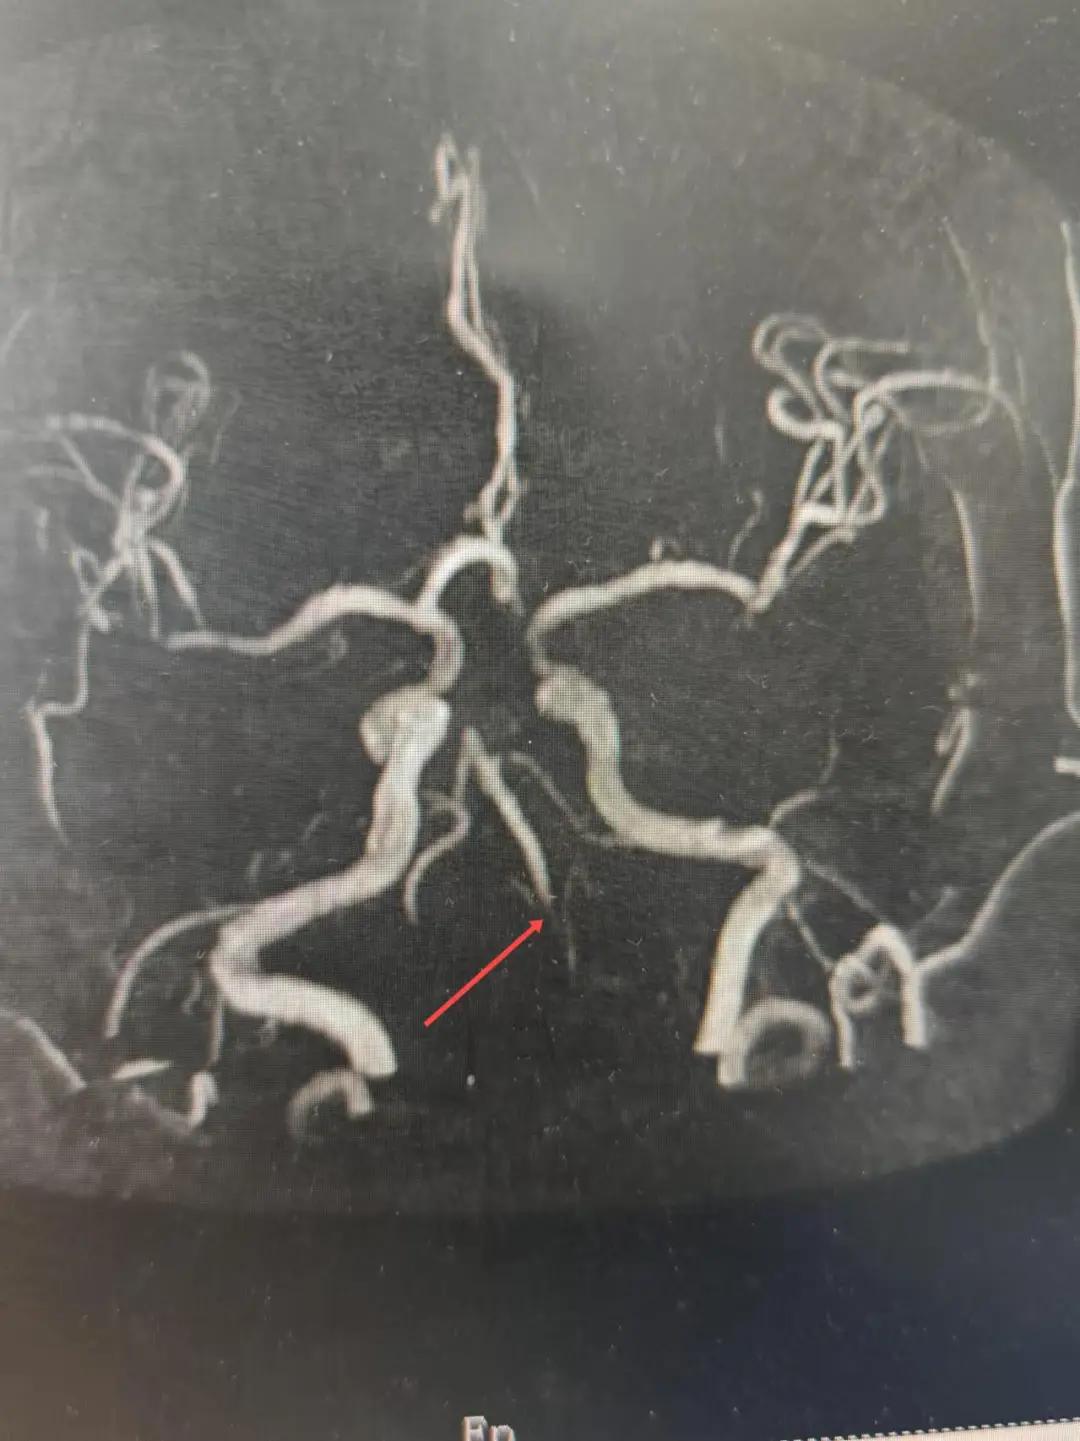

2024年12月19日,漯河市中醫(yī)院腦一科收治了一位79歲的女性患者?;颊咴谌朐呵?小時(shí)出現(xiàn)言語(yǔ)不利,右側(cè)肢體無(wú)力。腦一科醫(yī)師關(guān)卓杰接診后,全面評(píng)估患者病情,給予其靜脈溶栓,并急查頭顱MR。影像可見(jiàn)腦干、雙側(cè)枕葉、左側(cè)海馬旁回及丘腦新發(fā)梗塞灶,基底動(dòng)脈閉塞?;颊咴陟o脈溶栓完畢后仍出現(xiàn)陣發(fā)性言語(yǔ)不利、右側(cè)肢體無(wú)力、頭暈。立即進(jìn)行科室間會(huì)診,副主任醫(yī)師彭壯考慮患者出現(xiàn)上述癥狀與其基底動(dòng)脈閉塞后顱內(nèi)動(dòng)脈代償不良有較大關(guān)系,且基底動(dòng)脈閉塞有較高的致死率與致殘率,建議行急診取栓,降低患者死亡及殘障風(fēng)險(xiǎn)。家屬了解病情,知情同意后要求行介入治療。

磁共振MRA提示基底動(dòng)脈閉塞